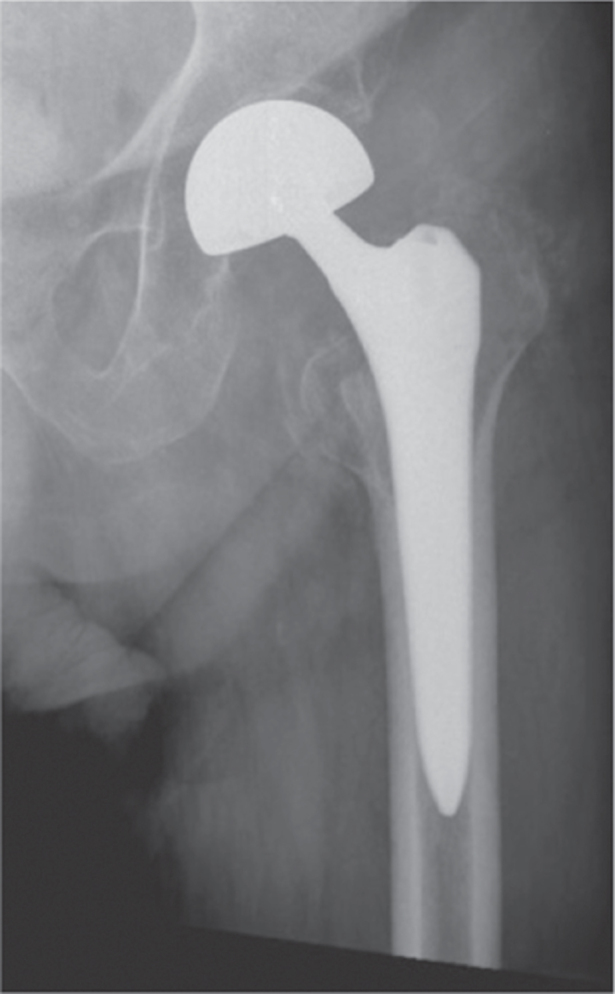

Methods: In this retrospective study, a total of 314 patients who were operated on for hip fractures were included study. Patients were then divided into four groups based in their implant types: long-stem cementless bipolar hemiarthroplasty (n = 124; 102 female, 22 male; mean age = 84.2 ± 6.4 years), standard-stem cementless bipolar hemiarthroplasty (n = 74; 48 female, 26 male; mean age = 83.5 ± 6.9 years), antegrade intertrochanteric nail (n = 61; 35 female, 26 male; mean age = 78.5 ± 6.8 years), and total hip arthroplasty (n = 55; 34 female, 21 male; mean age = 72.5 ± 4.3 years). Data including gender, age, duration from injury to surgery, American Society of Anesthesiologists (ASA) score, comorbidities, use of antiplatelet agents, Barthel Index of Activities of Daily Living, type of anesthesia, operation time, preoperative hemoglobin values, blood transfusions given, duration of hospital stay, complications, and type of fracture were recorded.

Abstract Image